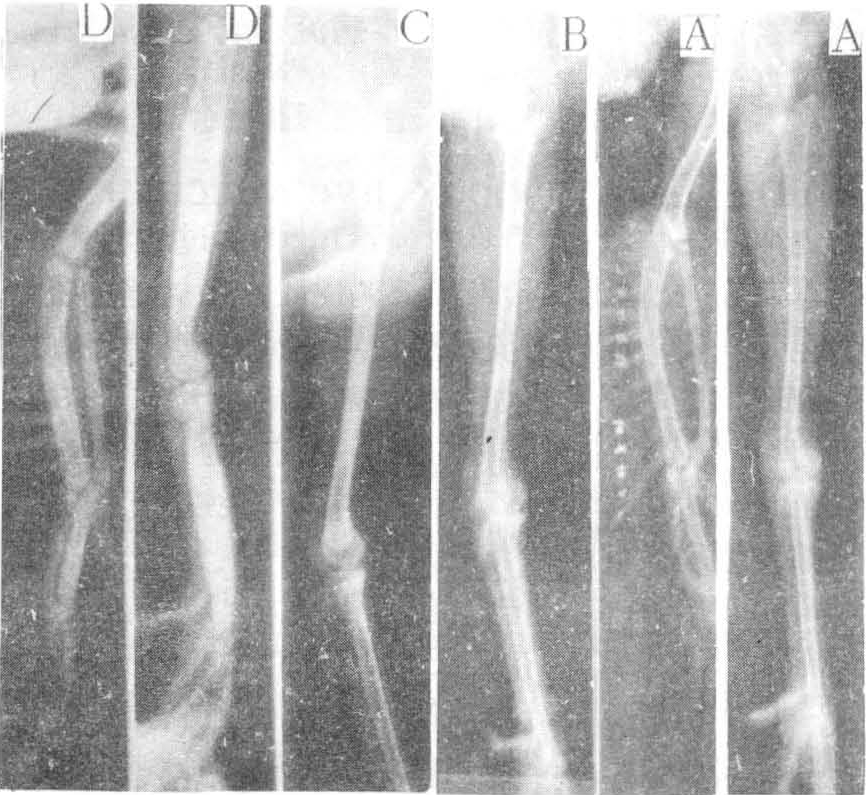

本病X线征为泛发性骨质增生硬化,全身骨骼均可发生,但以四肢长骨最常见,通常左右对称。X线表现骨密度增加,骨皮质增厚,骨髓腔变窄甚至闭塞。少数病鸡可发生长骨梭状畸形。X线所见可分为四种病理类型。①四肢长骨骨干骨质增生与梭状畸形:以胫骨、跖骨、尺骨、桡骨及臂骨明显,骨干中段横径可比正常增大1~4倍,骨膜与骨内膜均可见增生硬化,骨髓腔狭窄或消失,干骺端发育障碍,骺软骨及籽骨骨化延迟,骨骺板与关节间隙增宽。此型多限于仔鸡,为有特征性症状的临床型病例,但较少见。②泛发性骨质硬化无骨骼畸形:病变主要在胫骨、尺骨、桡骨、乌喙骨及锁骨,皆为骨内膜增生硬化,其他骨骼可有不同程度硬化,但均无骨骼外形的肿大畸形。③局限性骨内膜增生:病变多限于胫骨骨干,少数可波及股骨或尺、桡骨,骨皮质增厚,其内缘与髓腔界限不清晰或呈层状增生。有些骨髓腔密度亦见增高。④小灶性增生硬化:主要限于胫骨,亦可见于桡、尺骨,呈小局灶性增生,为骨皮质内缘或骨髓腔内明显小结节样致密阴影,病灶可以保持稳定,少数可发展扩大。以上三种类型中以前两种较多见,均无临床症状,为隐性型病例(图)。(陈白希)

不同类型鸡骨质石化病四肢侧位X线照片